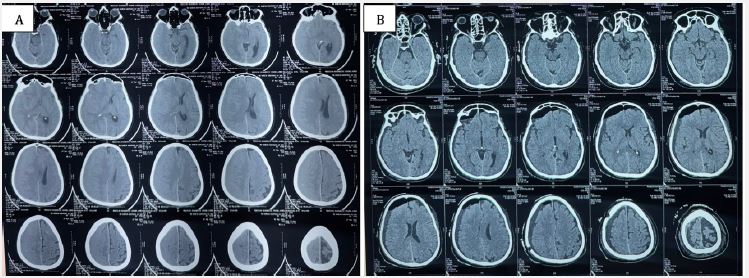

An NCCT head revealed a subacute SDH along the right fronto-parieto-temporal convexity with effacement of adjacent sulcal spaces, mass effect on the right lateral ventricle, and significant midline shift (Figure 1A). He was taken up for right-sided burr hole craniotomy and evacuation of hematoma under general anesthesia. Postoperatively, he showed marked improvement in sensorium and resolution of headache, with improvement in left-sided power to near normal.

Given his recent cardiac intervention, antiplatelet therapy was restarted postoperatively after discussion with cardiology. The patient was discharged with an intact sensorium and advised follow-up (Figure 1B).

Figure 1: (A) Preoperative NCCT (Non contrast computerized tomography) scan of head showing Subacute subdural hematoma seen in right fronto-temporo parietal region with mass effect over underlying brain parenchyma resulting in effaced adjacent cortical sulci and partial effacement of right lateral ventricle with a midline shift towards left side.

(B) Postoperative NCCT head showing burr holes in right frontal and parietal bone with decrease in midline shift.